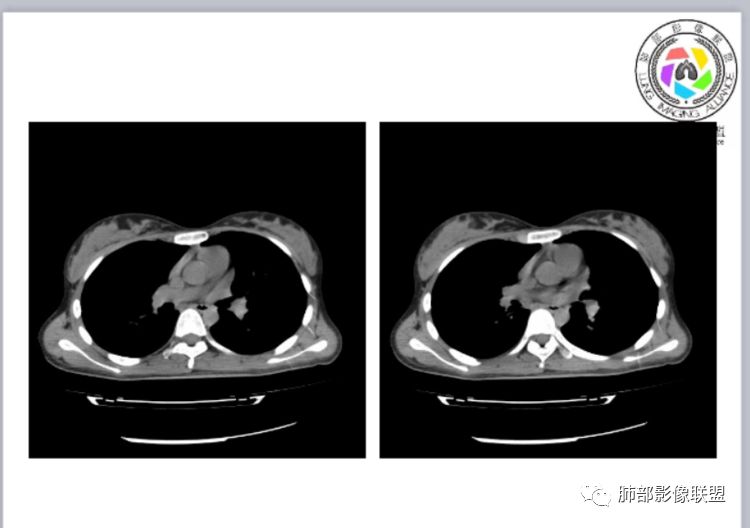

CTPA(CT断层肺血管造影)是对疑似PE患者肺血管系统成像的首选方法,可直观判断肺栓塞的程度和形态,以及累及部位及范围,可以从直接或间接征象进行诊断,但是对亚段及远段肺动脉血栓敏感性较差,联合肺动脉造影可以使PE诊断敏感性增强。

CTPA直接征象:

1、肺动脉中央部分充盈缺损

2、偏心性或附壁充盈缺损

3、骑跨型血栓

4、完全型充盈缺损,动脉截断,远端动脉分支内无造影剂

CT平扫及间接征象:

1、一个或多个胸膜下斑片高密度影(梗死、出血、肺不张、肺水肿、炎性渗出),典型为胸膜下楔形影 ,尖端指向肺门

2、肺动脉高压(中心肺动脉扩张),有时可见肺动脉区高密度影。

3、肺血减少

4、马赛克灌注

5、膈肌升高、胸腔积液、心包积液

1.临床:本例病人有服用雌激素史,是发生肺栓塞的危险因素,以胸痛起病,后有咯血症状,符合PE的临床表现;

2.实验室检查:明显的D-二聚体升高。虽然D-二聚体升高并不能确诊PE,但是明显升高一定要高度警惕肺栓塞的风险。

3.影像:病变胸膜下多发斑片影,提示与血管有关,早期病变为渗出,应该是早期的炎性渗出,病灶抗感染治疗后实变区增多、变大,临床症状又出现咯血,CT上应该合并了肺泡出血、梗死、肺不张及肺水肿;

以上都高度提示肺栓塞,因积极行肺动脉成像检查!